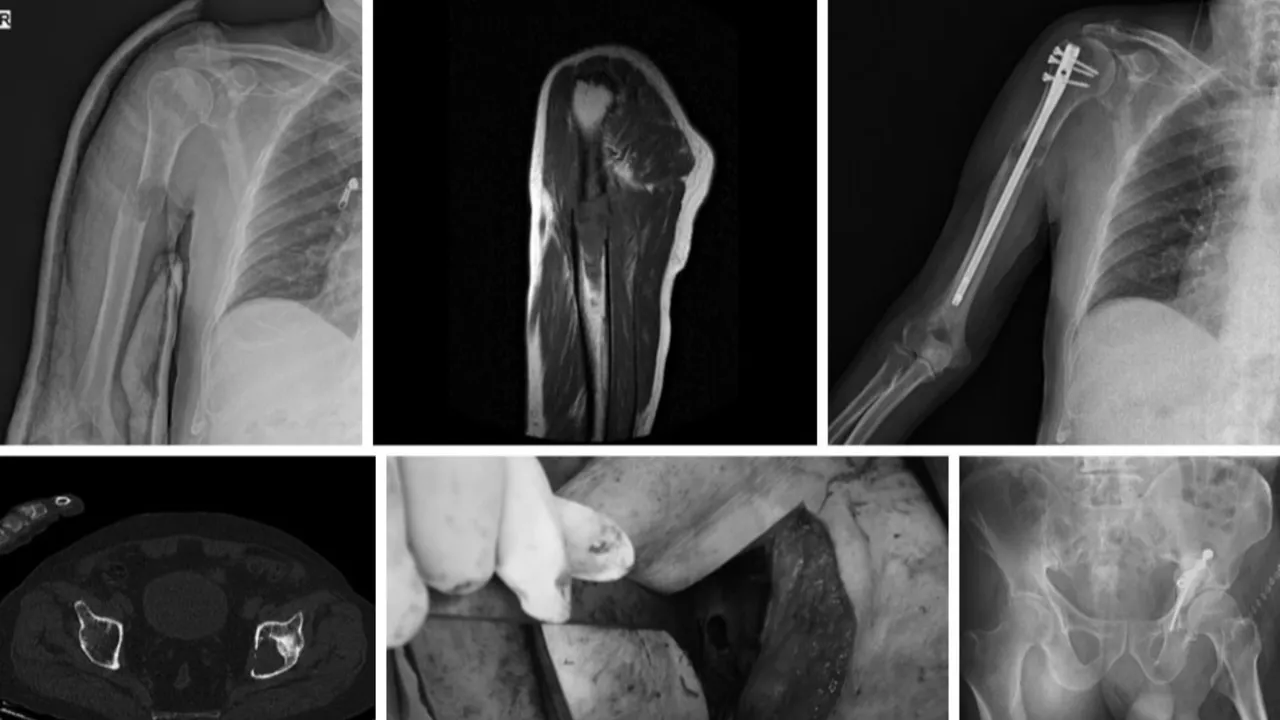

Multipl miyelom, kemik iliğinde (kemiklerin içindeki süngerimsi malzeme) ortaya çıkıyor ve yayılıyor. Normalde enfeksiyonla savaşmak için antikor üreten plazma hücreleri (beyaz kan hücreleri), kanserleşip kontrolsüz bir şekilde çoğalmaya başlıyor. Bu kanserli hücreler, kemik iliğinde birden fazla bölgede toplanma eğilimindedir, dolayısıyla ismindeki 'multipl' (çoklu) kelimesi buradan geliyor. Yorgunluk, sırt ağrısı ve tekrarlayan enfeksiyonlar (çünkü kanser aynı zamanda bağışıklık sistemini de baskılıyor) gibi belirtiler belirsiz olabileceğinden, teşhis genellikle gecikiyor. Hastaların üçte biri ancak hastalığın tetiklediği kemik kırıkları veya böbrek yetmezliği ile acil servise başvurduklarında tespit ediliyor. Miyelom hücreleri, kemik yiyen hücreleri (osteoklastlar) aktive eden ve kemik yapıcı hücreleri (osteoblastlar) devre dışı bırakan kimyasal mesajlar salgılıyor. Ardından, kemik içeriden aşınarak kırıklara neden oluyor ve bu nedenle kalsiyum kana karışabiliyor.

Yakın zamana kadar miyelom, derinlerde kemik iliğinde gizlenerek ilaçların ulaşmakta zorlandığı için tedavisi en zor kanserlerden biriydi. Halihazırda uygulanan tedaviler arasında kemoterapi, radyoterapi, miyelom hücrelerini hedefleyen ilaçlar ve kemik hasarını azaltmak için tasarlanmış bifosfonatlar gibi ilaçlar bulunuyor.

KÖK HÜCRE NAKLİNDE, HASTALARIN ÇOĞUNDA KANSER GERİ DÖNÜYOR

Ayrıca, yılda binlerce hasta, doktorların hastanın kanından kök hücreleri çıkarıp, miyelom kanser hücrelerini yok etmek için yüksek doz kemoterapi uyguladığı ve ardından sağlıklı yeni kemik iliği oluşturmak üzere kök hücreleri vücuda geri infüze ettiği bir kök hücre nakli de geçiriyor. Ancak bazı çalışmalar, kök hücre nakli hastalarının üçte ikisine kadarında kanserin üç yıl içinde geri döndüğünü gösteriyor.